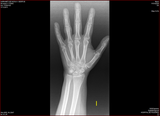

W22 Pols Gé 17-03-2011